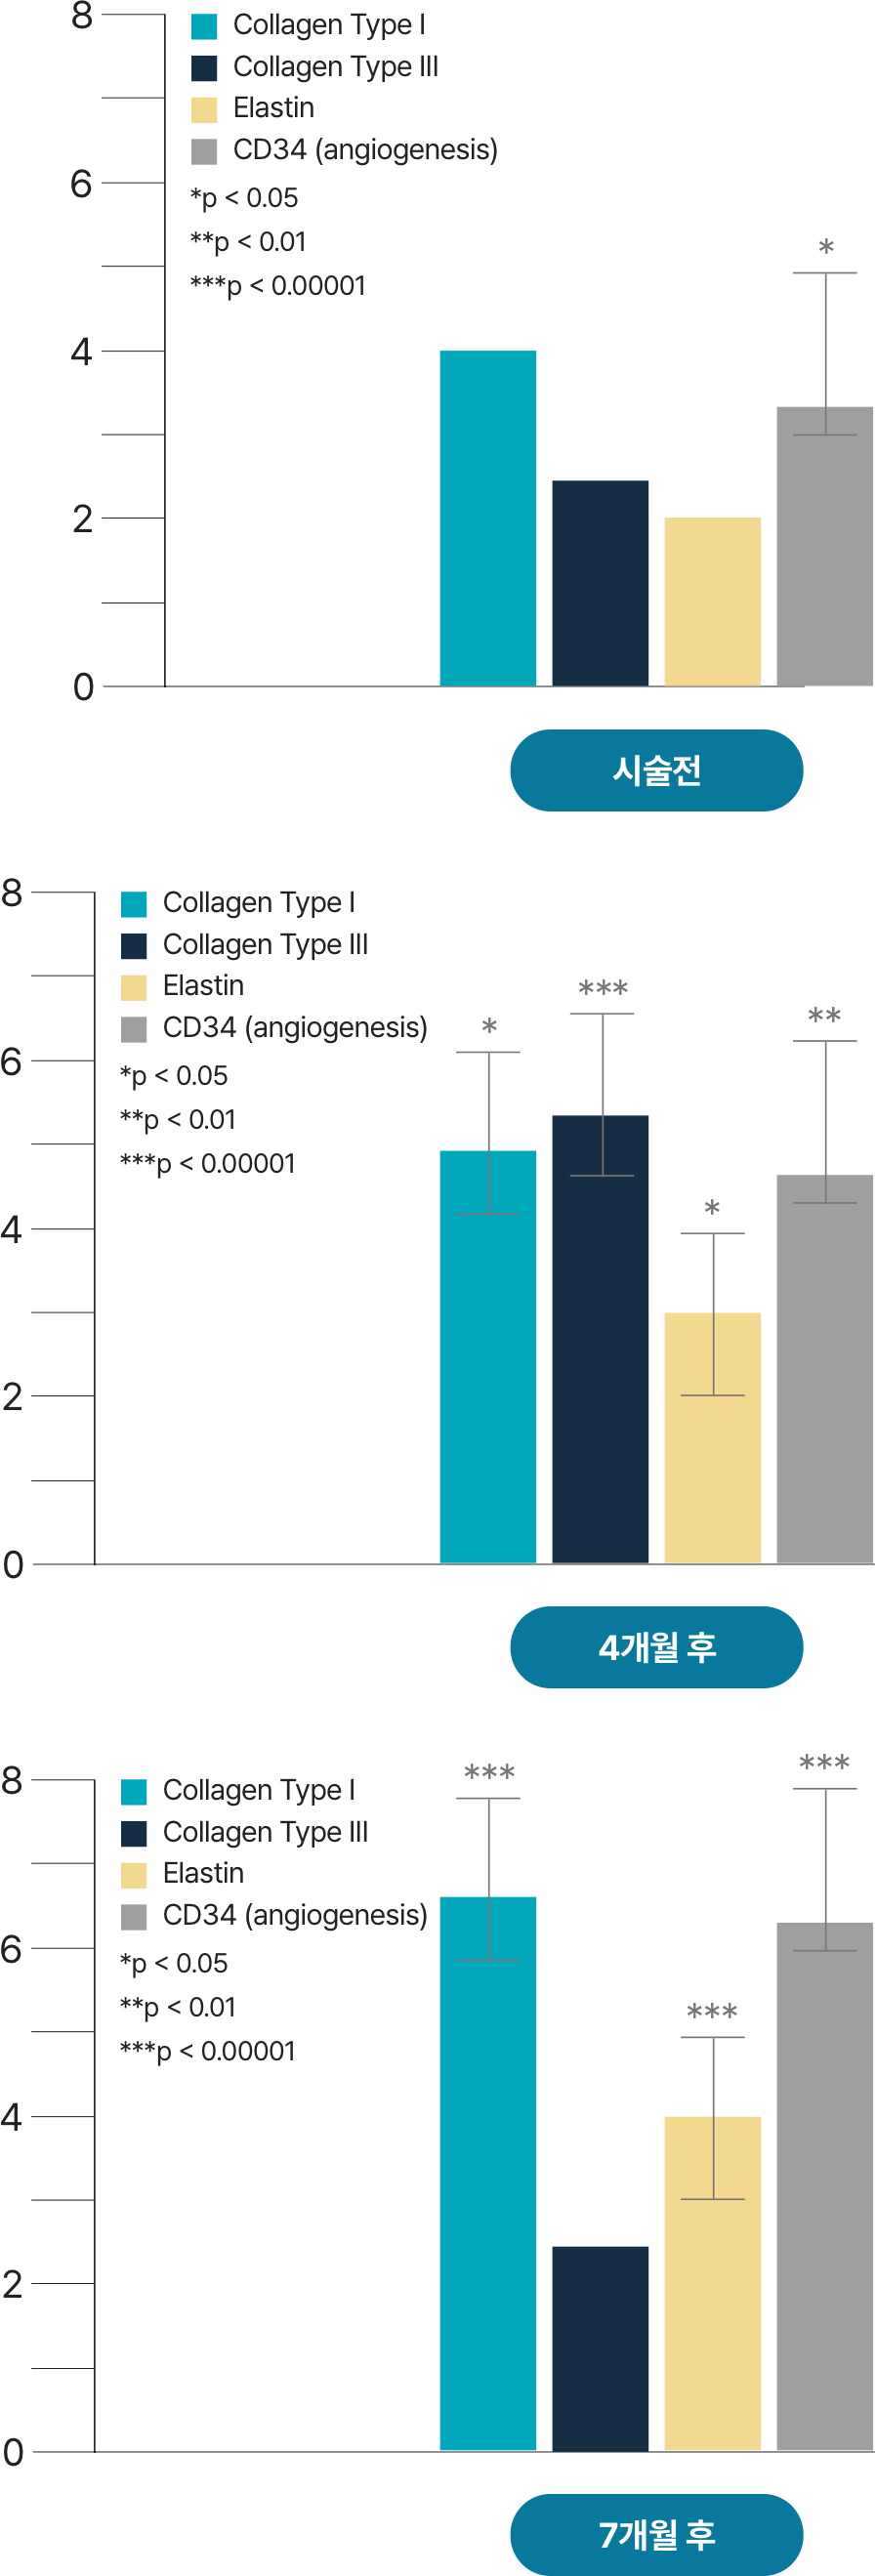

레디어스의 CaHA는 바이오 스티뮬레이터로

ECM 구성 성분 5가지를 만들어냅니다.

5가지 재생 성분은 약해진 피부 중심을 단단히 채워줍니다.

피부에 주입시켜 섬유아세포의 활성과 텐션을 회복하는 것은 바이오 스티뮬레이터인 레디어스의 가장 큰 특징입니다.

피부 탄력성, 두께감, 피부결 개선

조직회복, 콜라겐 1형의 구조적 지지

피부 탄력성, 피부 탄탐함

수분 보충, 피부 탄탄함

혈액 공급, 영양분 공급

민앤정의원 콜라겐 바이오 스티뮬레이터는 피부 스스로 되살아나는 근본적인 변화를 이끌어냅니다.

시술 직후, 피부와 주변 조직이 건강하게 재생되기 시작하고 콜라겐을 비롯한 탄력 성분들이 자연스럽게 활성화되며 피부 세포의 기능이 점차 정상화됩니다.

이러한 과정을 통해 피부는 다시 탄력을 찾고, 시간의 흐름에 맞서 되돌리는 듯한 턴에이징 효과를 경험하게 됩니다.